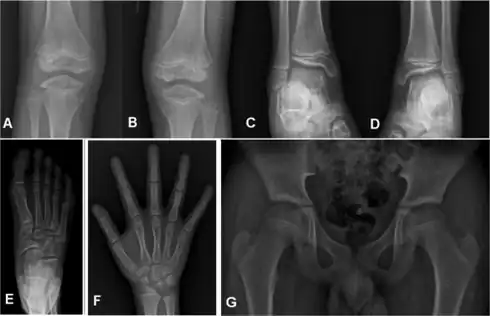

Children with autosomal dominant MED experience joint pain and fatigue after exercising. Their x-rays show small and irregular ossifications centers, most apparent in the hips and knees. There are very small capital femoral epiphyses and hypoplastic, poorly formed acetabular roofs.[1] A waddling gait may develop. Knees have metaphyseal widening and irregularity while hands have brachydactyly (short fingers) and proximal metacarpal rounding. Flat feet are very common.[2] The spine is normal but may have a few irregularities, such as scoliosis.